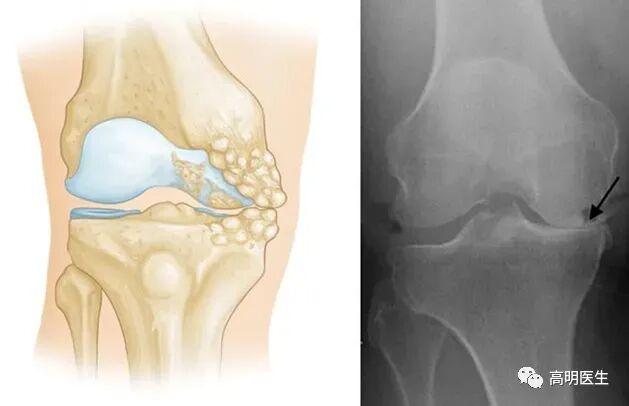

关节炎不是冻出来的

· 骨关节炎:最常见的类型,主要由关节软骨的退化引起。年龄增长、肥胖、过度使用关节、遗传因素等才是主要发病原因。

关节就像汽车轮胎,也有“使用寿命”。随着年龄增长,关节软骨逐渐磨损,弹性下降,最终出现骨赘(俗称“骨刺”),这就是骨关节炎的过程 。 只不过有些人的关节耐磨,有些人的不耐磨罢了。不仅人类,几乎所有脊椎动物都会得骨关节炎,但是对于一些关节负荷极小的动物(如蝙蝠、树懒等)发病率极低。这也说明骨关节炎是关节对磨损的自然反应。